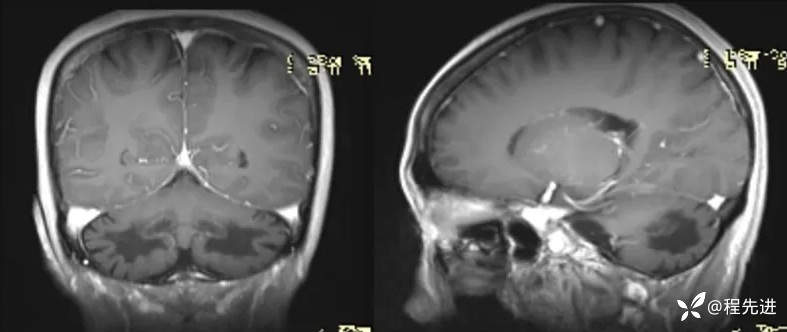

T1:

T2、FLAIR:

颈椎MRI平扫:

胸椎MRI平扫:

颅脑MRI增强: